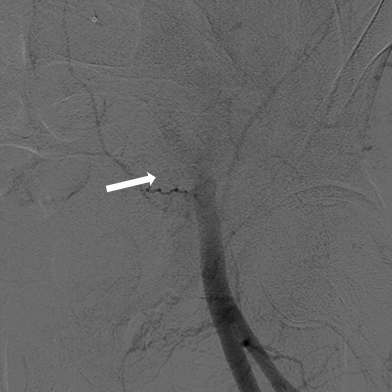

行急诊手术 腹主动脉及左侧股动脉造影

左侧股动脉见造影剂外渗